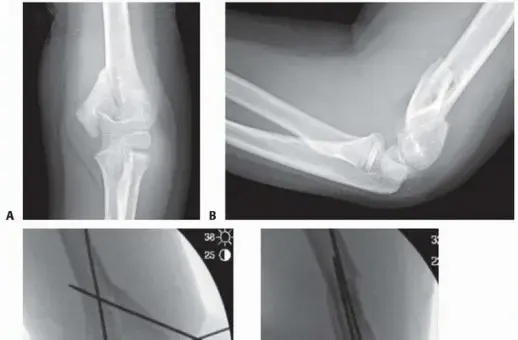

2. الأشعة السينية (X-rays):

• تُعد الأشعة السينية هي الأداة التشخيصية الأساسية للتحقق من وجود الكسر وتحديد نوعه وموقعه. سيتم أخذ عدة صور للكوع من زوايا مختلفة (أمامية-خلفية، جانبية، ومائلة) للحصول على رؤية شاملة للكسر.

• في حالة كسور الكوع من نوع T، قد تظهر الأشعة السينية بوضوح الانقسام الذي يشبه حرف T أو Y في نهاية عظم العضد، بالإضافة إلى أي تفتت أو إزاحة في القطع العظمية.

• الأشعة السينية مهمة أيضاً لتقييم صفائح النمو لدى الأطفال.